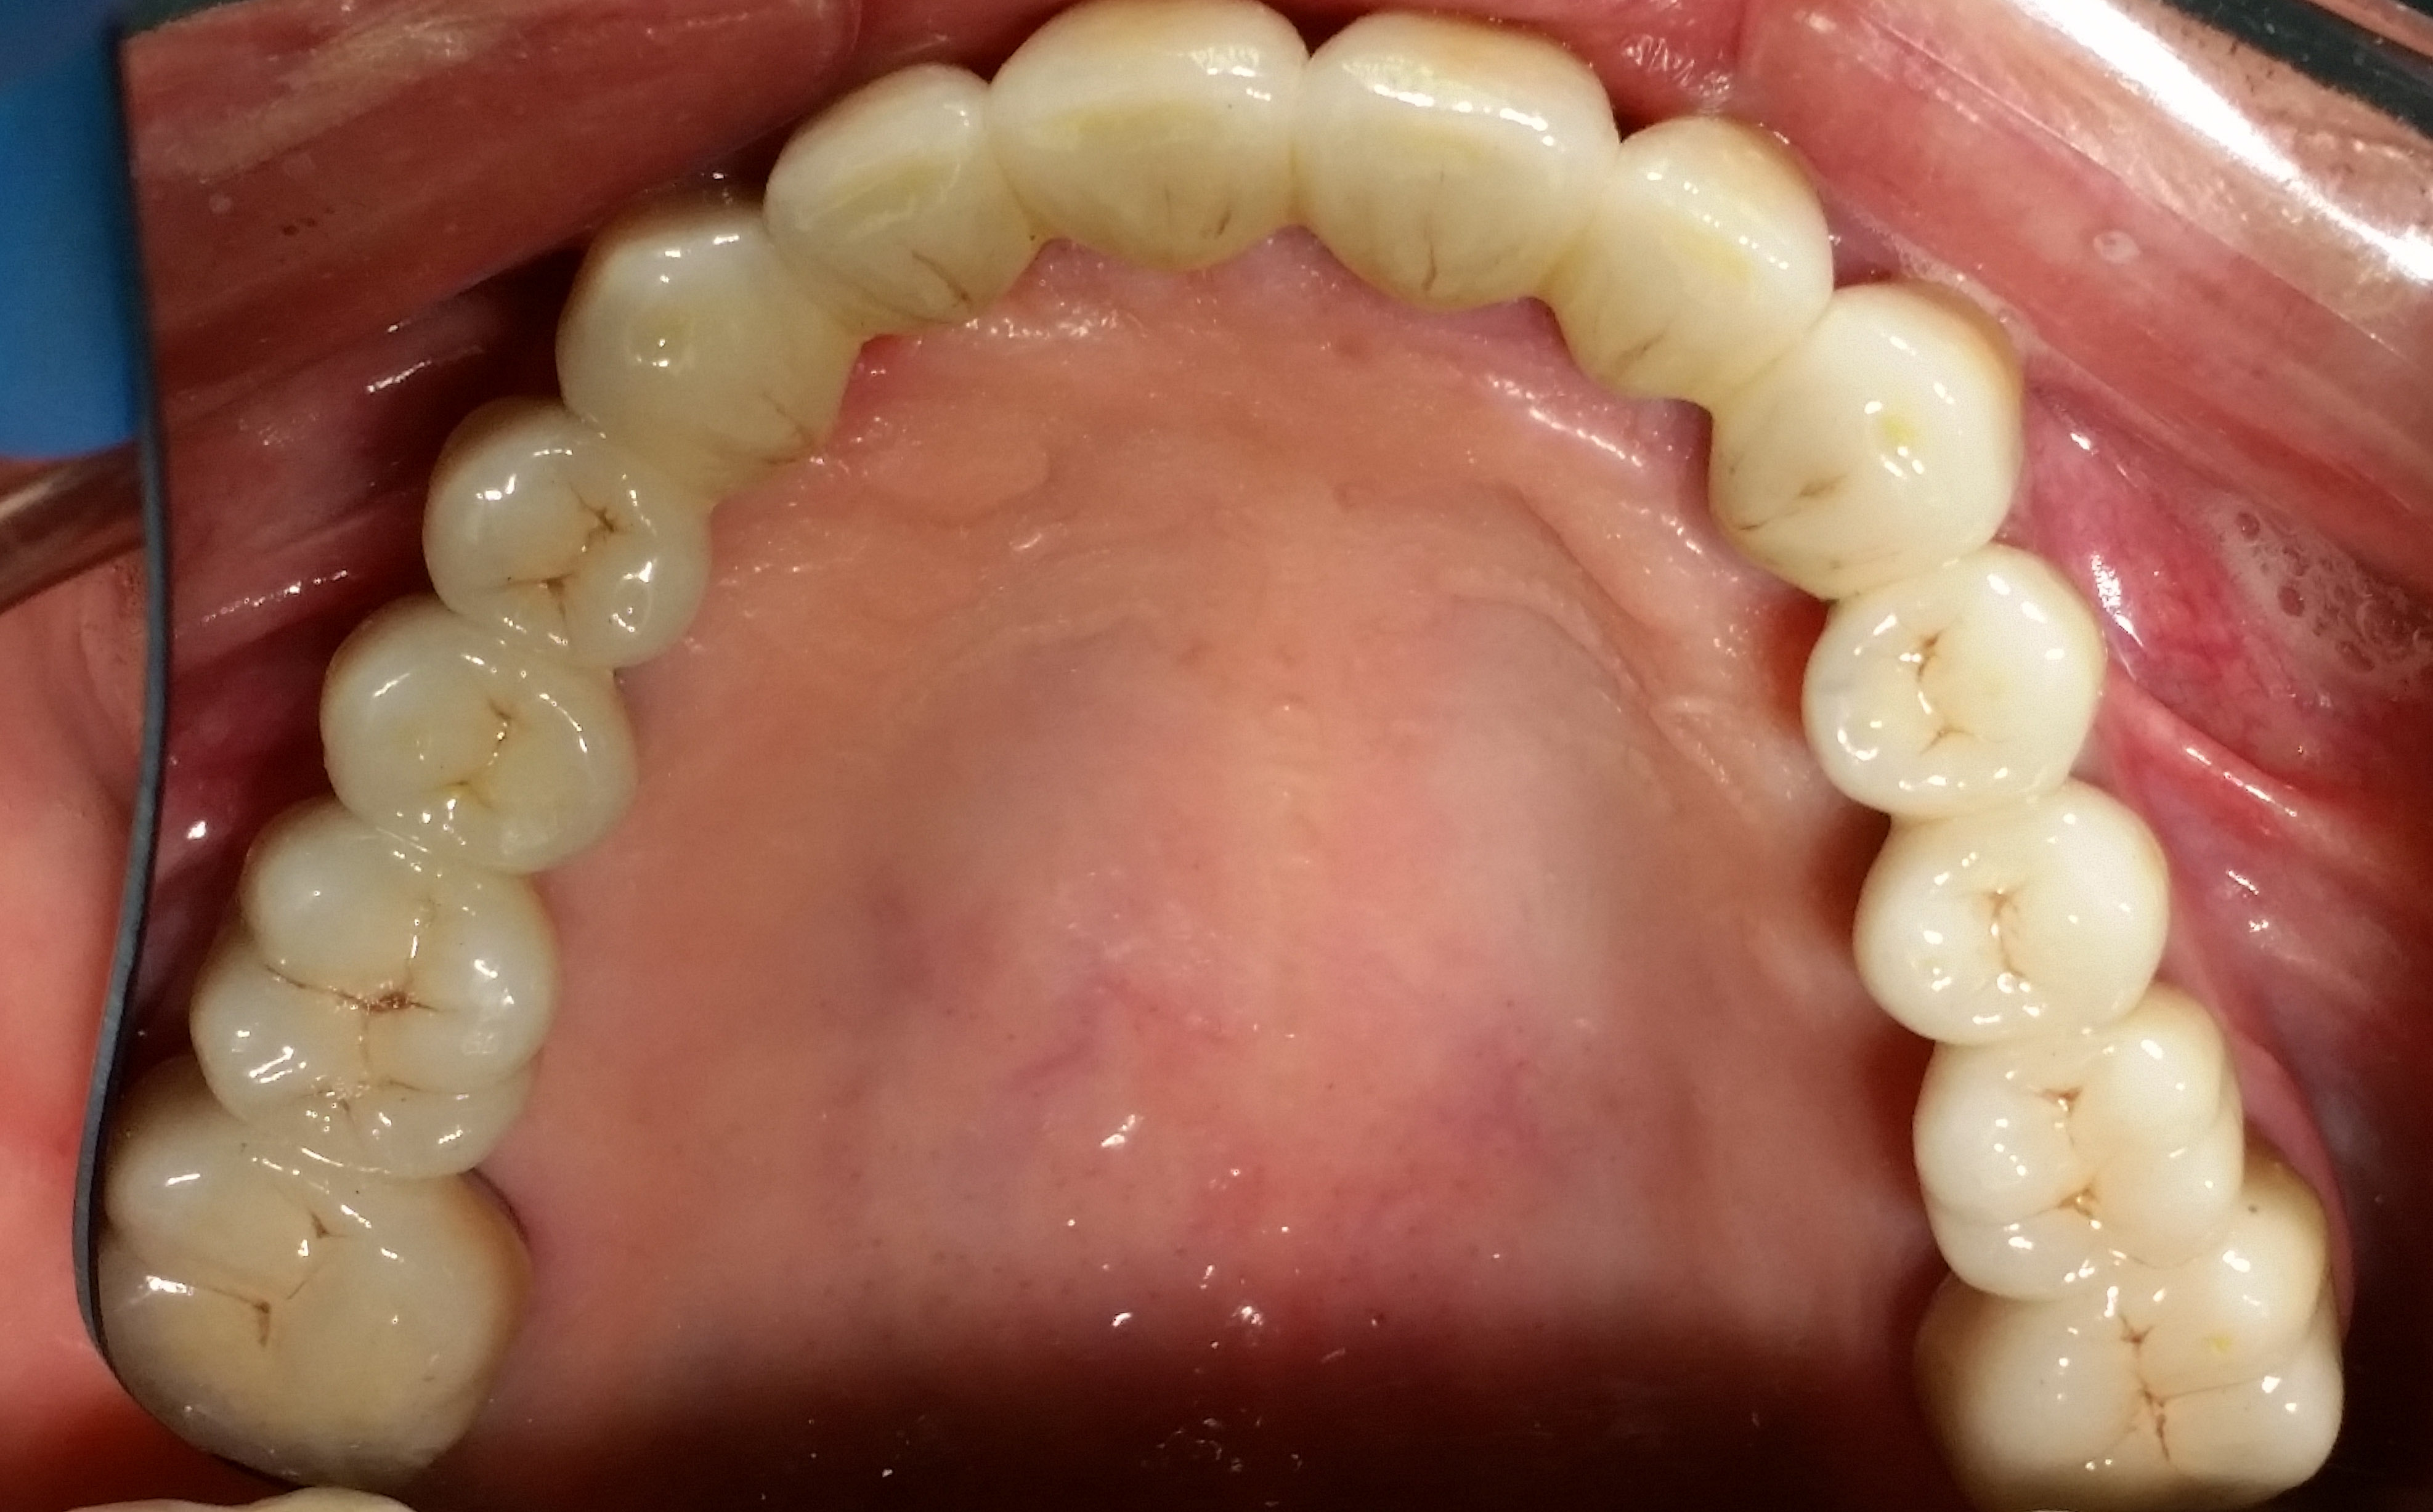

La paziente si presenta alla mia attenzione con scheletrato superiore sostenuto da elementi parodontopatici.Il chief complaint è chiaro:"Non voglio più sentire niente sul palato". Per motivi economici si esclude la soluzione chiurgico-implantare.

Si decide allora per una protesi totale superiore su barra.

Dopo la preventiva bonifica degli elementi irrecuperabili e la devitalizzazione degli unici 4 elementi utilizzabili, si confeziona una protesi totale superiore (senza palato) su barra con 4 ball-attachment a sua volta sorretta dagli elementi naturali precedentemente devitalizzati.